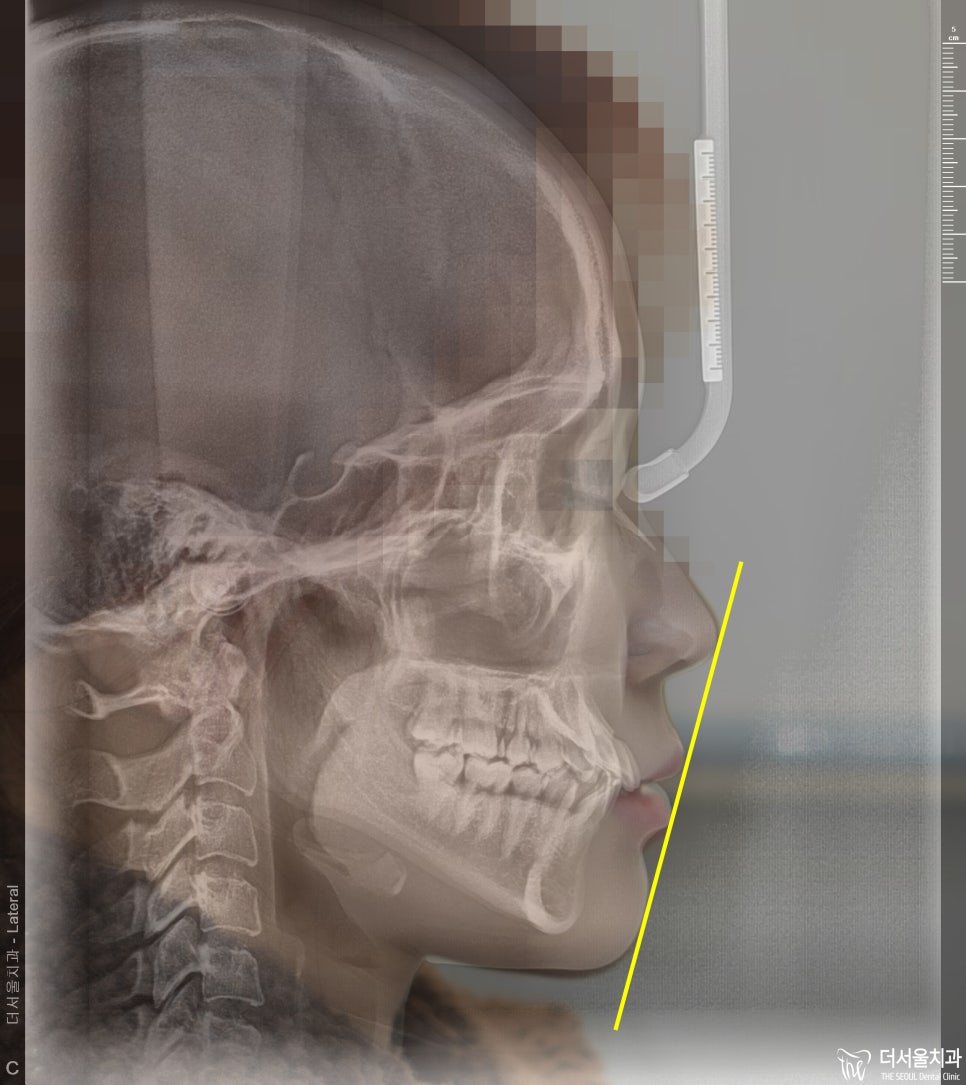

심미선이라는게 있습니다. 영어로는 Ricketts line(리케츠라인) 이라는건데 코 끝과

턱 끝을 일직선으로 이은 가상의 선을 뜻하는겁니다.

근데 이 분의 경우에는, 일직선 상에 입술이 위치되어 있는 것을 볼 수 있습니다.

돌출입 기준 으로는, 보통 입술이 이 심미선 바깥으로 튀어나가 있으면 돌출입 이라

부를 수 있는데 이 분의 경우에는 애매하죠?

심미선과 입술 위치가 서로 일치를 해야 예쁘다 라는 의견이 있고,

또 다른 쪽에서는 안쪽에 입술이 위치를 해야 예쁘다 라는 의견이 있습니다.

근데 핵심은 앞니들이 앞쪽으로 뻐드러져 있습니다. 즉, incisal angle 의 변화가 필요합니다.